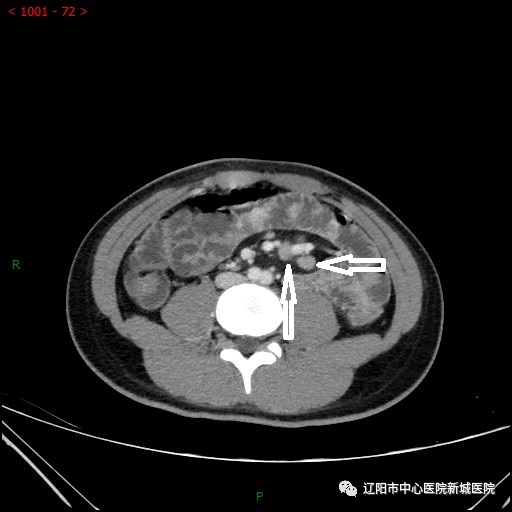

小腸腸壁節(jié)段性增厚并明顯均勻強(qiáng)化,管腔狹窄

軸位箭頭是淋巴結(jié)腫大